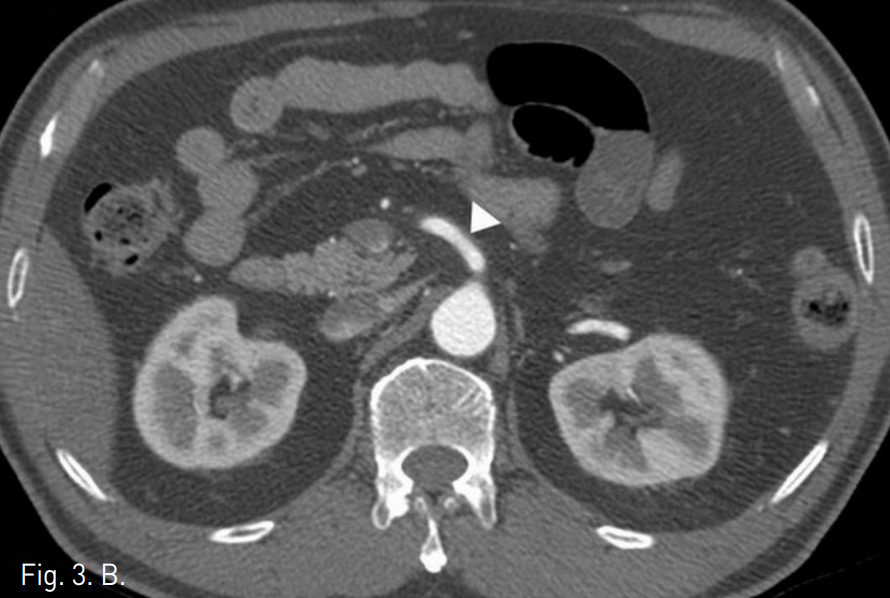

복부 CT에서 상장간막동맥(superior mesenteric artery, SMA)의 박리가 있었으며 중간결장동맥(middle colic artery)의 기시부가 경도로 좁아져 있고 가성 내강과 진성 내강의 혈류가 관찰되었다(Fig. 1). 같은 날 시행한 혈관조영술에서 상장간막동맥 기시부부터 회결장동맥(ileocolic artery) 분지부까지 침범한 동맥박리를 확인 하였다(Fig 2). 이 밖에 복강동맥과 하장간막동맥에는 특이 소견은 발견 되지 않았으나 변연 동맥 여러 곳이 동맥경화에 의한 좁아져 있었다. 소장과 대장의 동맥혈류가 유지되고 있어 스텐트삽입술은 시행하지 않았으며, 수축기 혈압 110mmHg, 심장박동 수 50~60회로 유지하며 보존적 약물치료를 하였다. 환자의 복통은 진정되었으며 7일 후 퇴원하였다. 5개월 후 추적검사로 시행한 복부 CT에서 상장간막동맥의 박리피판이 여전히 관찰되며 진성 내강과 가성 내강의 개통성을 확인할 수 있었고 기타 변연 동맥의 폐색은 없는 것이 확인되었다. 하지만 1년 추적 복부 CT에서는 가성 내강을 따라 혈전이 형성되었고(Fig. 3) 원위부로 혈관 폐색의 소견은 보이지 않았으며 장관의 허혈이나 경색 소견 또한 관찰되지 않았다. 2년 추적 CT에서 상장간막동맥은 정상화되었으며 박리나 동맥류 소견은 관찰되지 않았다.

Fig. 3

A, B. (A) The axial image of the one-year follow-up abdominal CT shows thrombosis of the entire false lumen of SMA (arrow). (B) The two-yer follow-up CT shows normal SMA without dissection or aneurysm (arrow head).